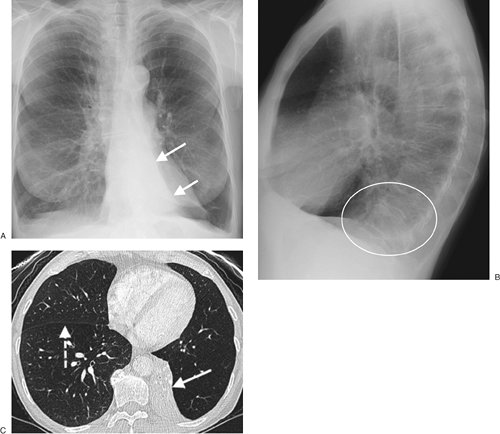

FIGURE 11-15. Left lower lobe collapse. A: PA chest radiograph of a 65-year-old woman shows inferior displacement of the left major fissure (arrows) and a triangular area of abnormal opacity projected over the left heart. B: Lateral view shows abnormal opacity overlying the lower spine (circle), the so-called spine sign. C: CT shows the collapsed left lower lobe hugging the spine, outlined laterally by the inferiorly displaced major fissure (solid arrow). Note the normal position of the right major fissure (dashed arrow).